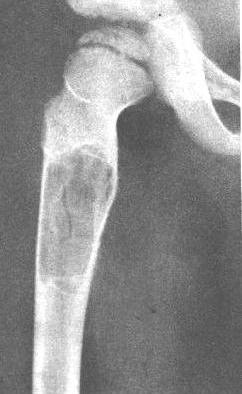

股骨骨囊肿。股骨上段骨干内椭圆形透光区,长径顺骨纵轴,边缘锐利,周围有薄层硬化增白。

1.单房性囊肿呈一个圆形或卵圆形界限清晰、密度均匀的透亮区,其中无骨间隔。多房性者其中则可见大的分房状现象,骨间隔大部分与长骨纵轴垂直。

2.病变以沿骨长轴发展为主,常有轻度膨胀,但很少向周围膨胀。膨胀使骨皮质变薄,但不致破裂,亦无骨膜反应。